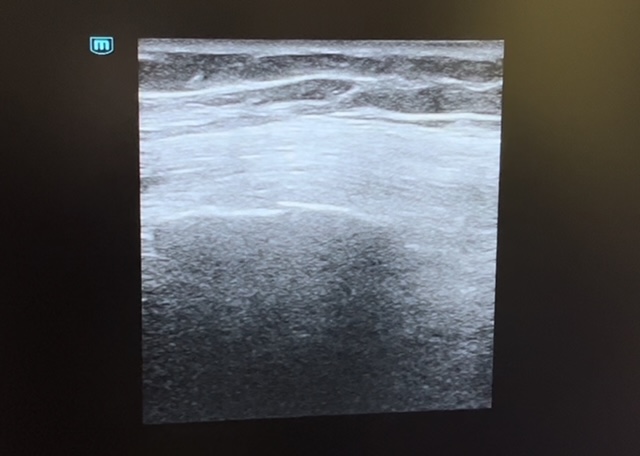

Se evidencia en la ecografía pulmonar sobre el 7º y 8º arco costal izquierdo una posible línea de fractura con falta de contigüidad en los rebordes costales sin evidenciar signos de neumotórax.